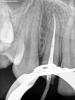

zybnaya feya Опубликовано 23 мая, 2011 Поделиться Опубликовано 23 мая, 2011 (изменено) Не поняла последнего снимка. Он что со спределром сделан? А так обтурация мне очень даже нравится. Без пор и паффов. У термафилов естественно конртастность выше будет,т.к носитель еще имеется. Изменено 23 мая, 2011 пользователем zybnaya feya Ссылка на комментарий

Гость razor Опубликовано 23 мая, 2011 Поделиться Опубликовано 23 мая, 2011 Это мастерштифт, снимки просто местами перепутаны Ссылка на комментарий

zybnaya feya Опубликовано 23 мая, 2011 Поделиться Опубликовано 23 мая, 2011 Это мастерштифт, снимки просто местами перепутаныТогда вообще не поняла зачем обмазывать стенки силлером и делать рвг с мастер-штифтом?Какую инфу даст он вам? Ссылка на комментарий

Гость razor Опубликовано 23 мая, 2011 Поделиться Опубликовано 23 мая, 2011 контроль припасовки штифта Ссылка на комментарий

zybnaya feya Опубликовано 23 мая, 2011 Поделиться Опубликовано 23 мая, 2011 контроль припасовки штифтаКак мне известно этот самый контроль делают,но без внесения силера. На последнем снимке штифт "припасован" на 2\3 длины. В чем заключасля контроль? Ссылка на комментарий

Гость razor Опубликовано 23 мая, 2011 Поделиться Опубликовано 23 мая, 2011 Как мне известно этот самый контроль делают,но без внесения силера. Если я сделаю снимок без силлера, потом вытащу штифт, внесу силлер, снова поставлю штифт - картина может поменяться, и в результате после пломбировки я получу не то, что хотел. а заново распломбировывать канал я не хочу. На последнем снимке штифт "припасован" на 2\3 длины. В чем заключасля контроль?точно не на 2/3 Ссылка на комментарий

zybnaya feya Опубликовано 24 мая, 2011 Поделиться Опубликовано 24 мая, 2011 точно не на 2/3http://s51.radikal.ru/i133/1105/4b/dd6a6605eaca.jpgне,на 2\3,5 Это ведь кончик гутины.или я ошибаюсь? Если я сделаю снимок без силлера, потом вытащу штифт, внесу силлер, снова поставлю штифт - картина может поменяться, и в результате после пломбировки я получу не то, что хотел. а заново распломбировывать канал я не хочу. Это не так. если вы сделаете снимок с чистой гуттой,то увидите,что она до апекса еще 4 мм точно не доходит и нужно калибровать другую. А хождения с силлером закончаться тем,что вы пока рвг сделаете,пока опять в кресло усадите,то силлер может подстыть и ничего вы тогда вообще толком не обтурируете .Это касается SealApecs и Acroseal например. Ссылка на комментарий